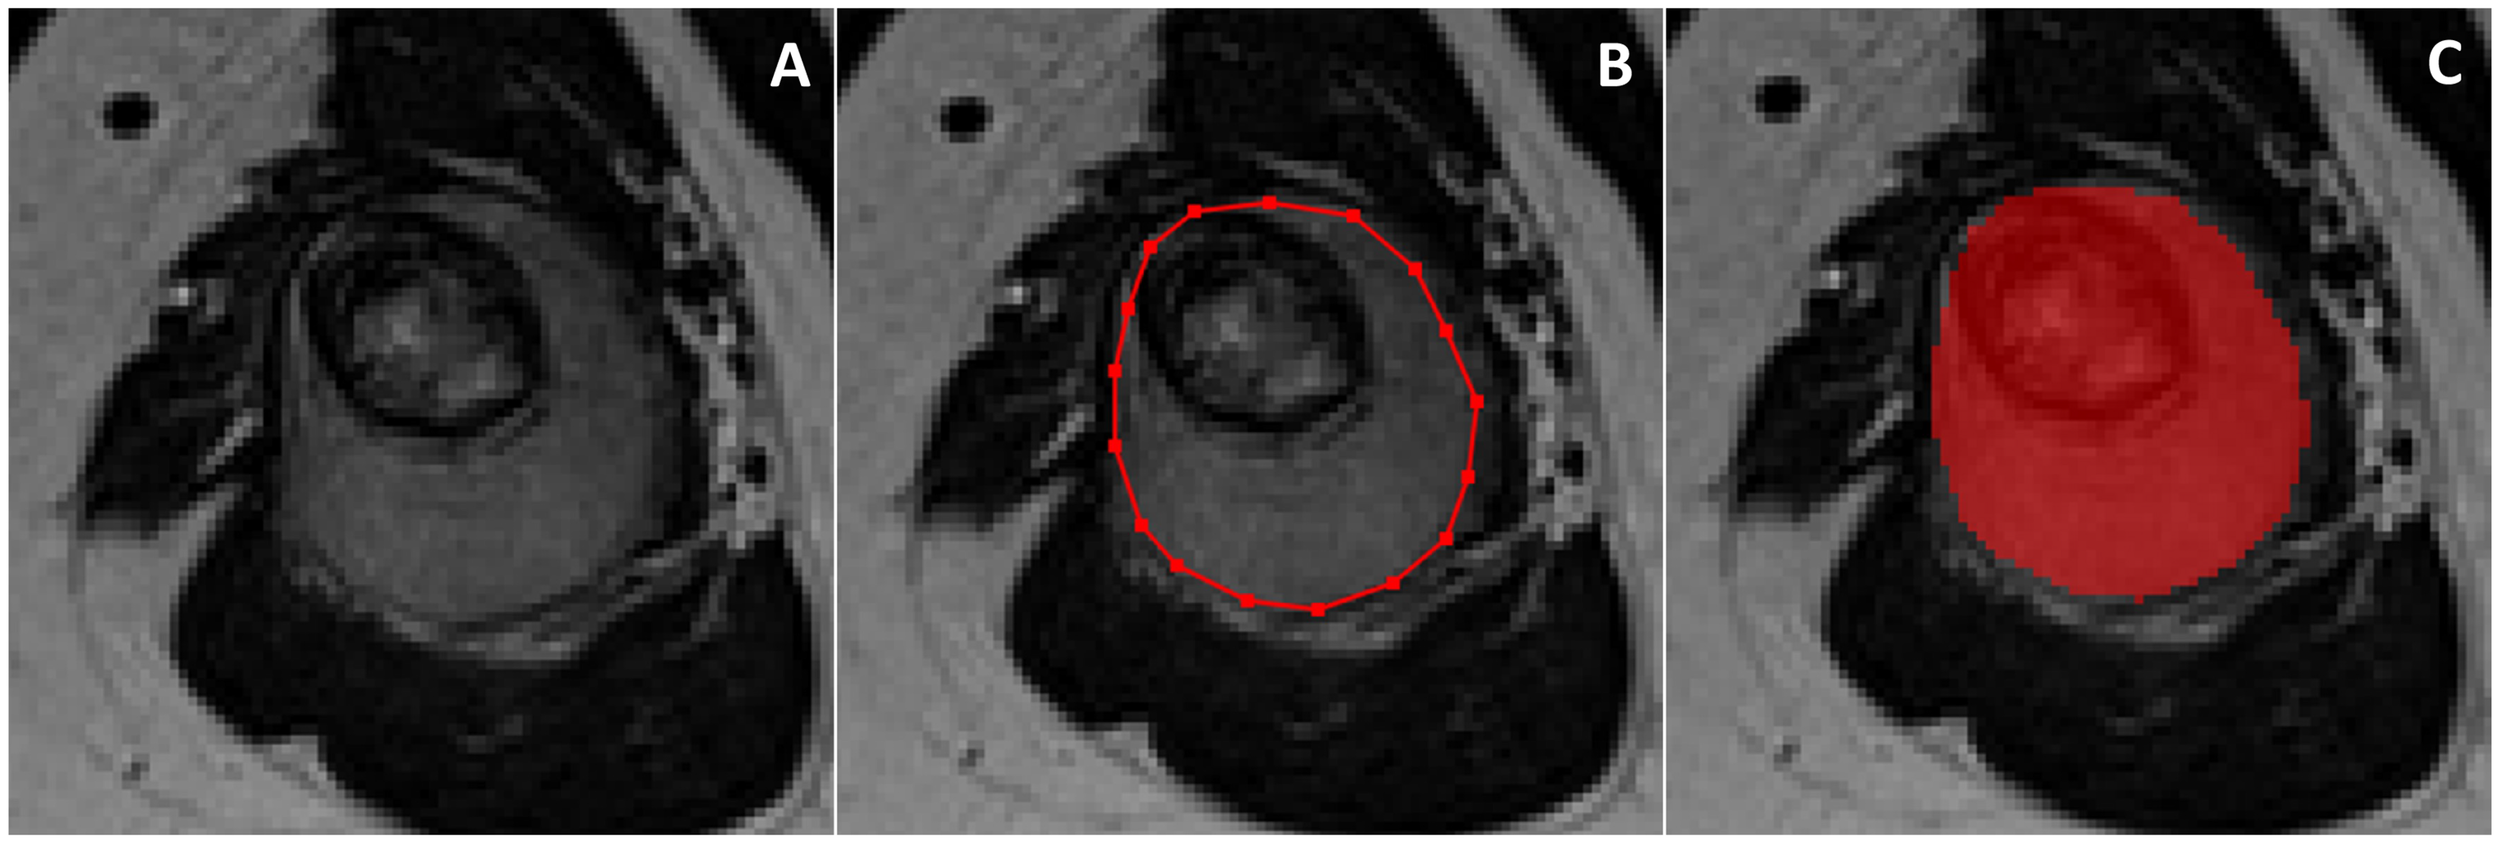

Reproducibility analysis was performed to evaluate the robustness of radiomic features. Feature reproducibility was assessed through small geometrical transformations of the ROIs mimicking multiple manual delineations and the potential sources of intra- and inter-observer variability when multiple ROIs are drawn by the same or different readers, respectively (16, 17). Different translations of the ROI in the positive and negative direction of the x and y axes were applied. The entity of the translation was 10% of the length of the bounding box including the tumour (Figure 2). For each patient, radiomic features were extracted from five different ROIs, namely the original and 4 translated ROIs. ICC was used to quantify reproducibility, and radiomic features were considered stable if ICC > 0.75 (9). Among stable features, further dimensionality reduction was performed through collinearity and significance analysis. Collinearity was evaluated using Pearson correlation coefficient (r). The threshold for collinearity was set as r = 0.8. If a pair of features had high collinearity, the one with higher collinearity with others was excluded. Significance analysis addressed the ability of radiomic features to discriminate between good and poor responders. Wilcoxon rank-sum test was used. Radiomic features with statistically different distribution between these two groups (p-value < 0.05) were kept and ranked by their p-value.

Figure 2 Original (green) and translated (red) version of 2D region of interest drawn around tumor borders on T2-weighted axial image.